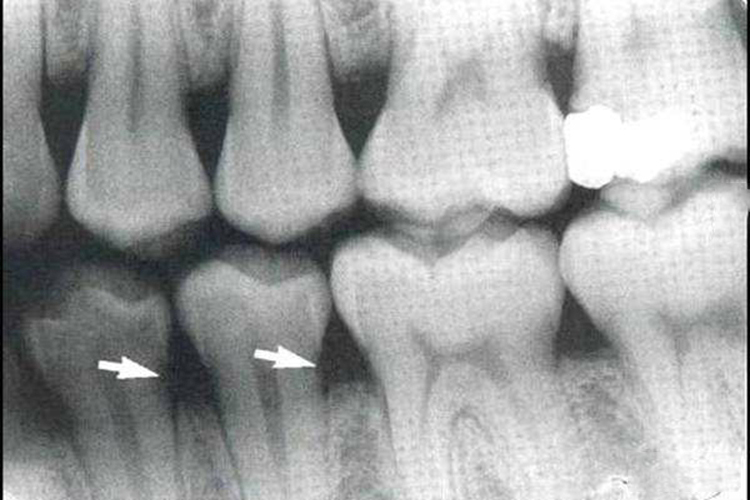

常见牙齿异常为龋齿。对于隐蔽的龋损,在不能直接视诊,且探诊也有困难时,可通过X线片检查辅助诊断,如邻面龋、潜行龋和充填物底壁及周缘的继发龋。龋损区因脱矿而在牙体硬组织显示出透射度增大的阴影,确定诊断。